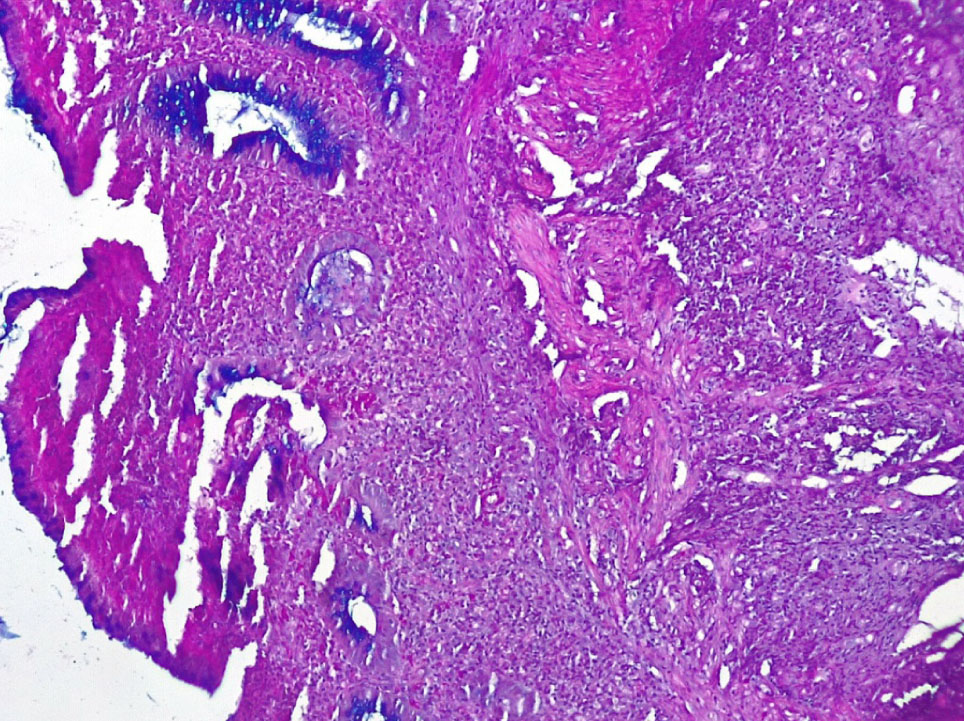

В основной группе морфологические и гистохимические изменения в СО толстой кишки были представлены язвами, нарушением регенерации цилиндрического эпителия и крипт, атрофией бокаловидных клеток, снижением продукции муцина клетками эпителия, различной степенью выраженности воспалительной реакции.

Язвенные дефекты СО толстой кишки были неглубокие и достигали собственную и мышечную пластинки. Вокруг язв отмечалась умеренно или резко выраженная лимфо-плазмоцитарная инфильтрация стромы с примесью нейтрофилов (++, +++), со сдавлением клеточным воспалительным инфильтратом крипт и развитием атрофии цилиндрического эпителия и крипт (++) (рис. 3).

Рис. 3. Основная группа: в СО толстой кишки – язвенный дефект с резко выраженной лимфоплазмоцитарной, нейтрофильной инфильтрацией, атрофией крипт и бокаловидных клеток. Окр. гематоксилином-эозином, ×200

В отдельных группах крипт отмечалось выраженная атрофия бокаловидных клеток (БК) (не более 3–4 на крипту) вплоть до полного их исчезновения (+++), развитие очагов гнойного криптита за счет выраженной нейтрофильной инфильтрации вокруг крипт (рис. 4).

Рис. 4. Основная группа: неравномерная атрофия крипт и бокаловидных клеток СО толстой кишки, выраженное хроническое воспаление стромы со скоплением нейтрофилов в отдельных криптах (гнойный криптит). Окр. гематоксилин-эозином, ×200